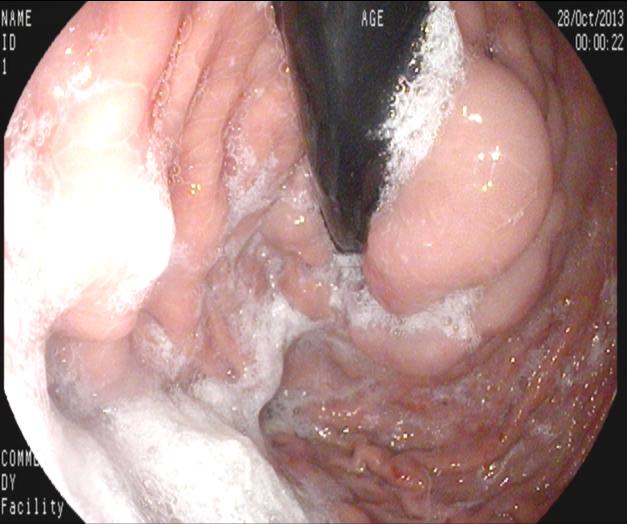

2013年10月13日28日行胃鏡檢查及鏡下套扎治療。

胃鏡下見(jiàn)胃底及食道皆有曲張的靜脈。

上圖為胃底曲張的靜脈團(tuán)